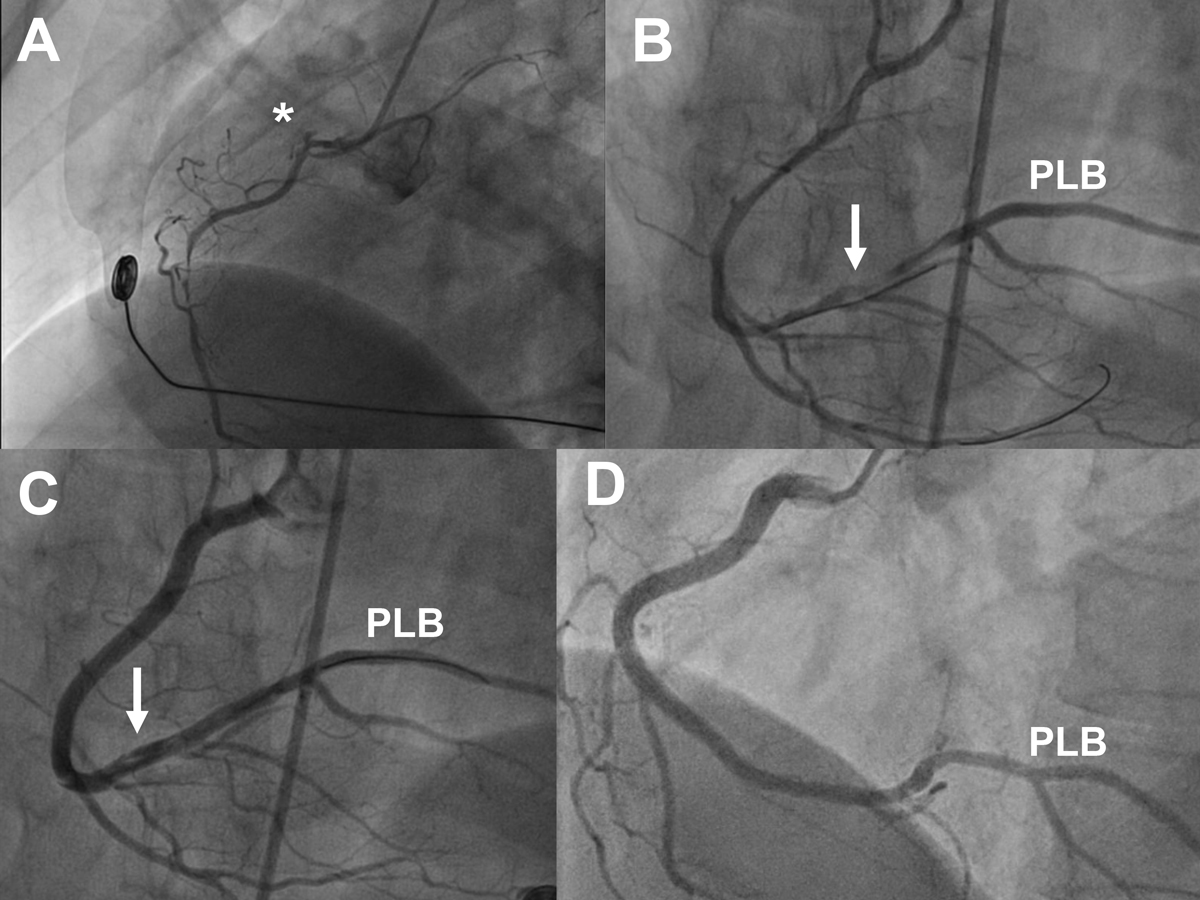

Figure 2 Angiograms of a 40-year-old female with inferolateral ST-segment elevation myocardial infarction, ongoing chest pain, and massive ECG ST-segment elevation at the time of angiography, treated by percutaneous coronary intervention. Panel A: left anterior oblique (LAO) 60° view showing extensive dissection of the right coronary artery (RCA) with minimal flow. B: cranial view showing extensive dissection of the RCA and the large posterolateral branch (PLB) after wiring of a large right ventricular branch and a side branch of the PLB. C: cranial view showing situation after correct wiring of the PLB and stenting of the mid to ostial RCA. The distal RCA and PLB are still dissected but were not stented. D: follow-up angiogram after 6 months. LAO 50°/cranial 15° view showing patent stents and angiographic healing of the dissection in the distal RCA and PLB.